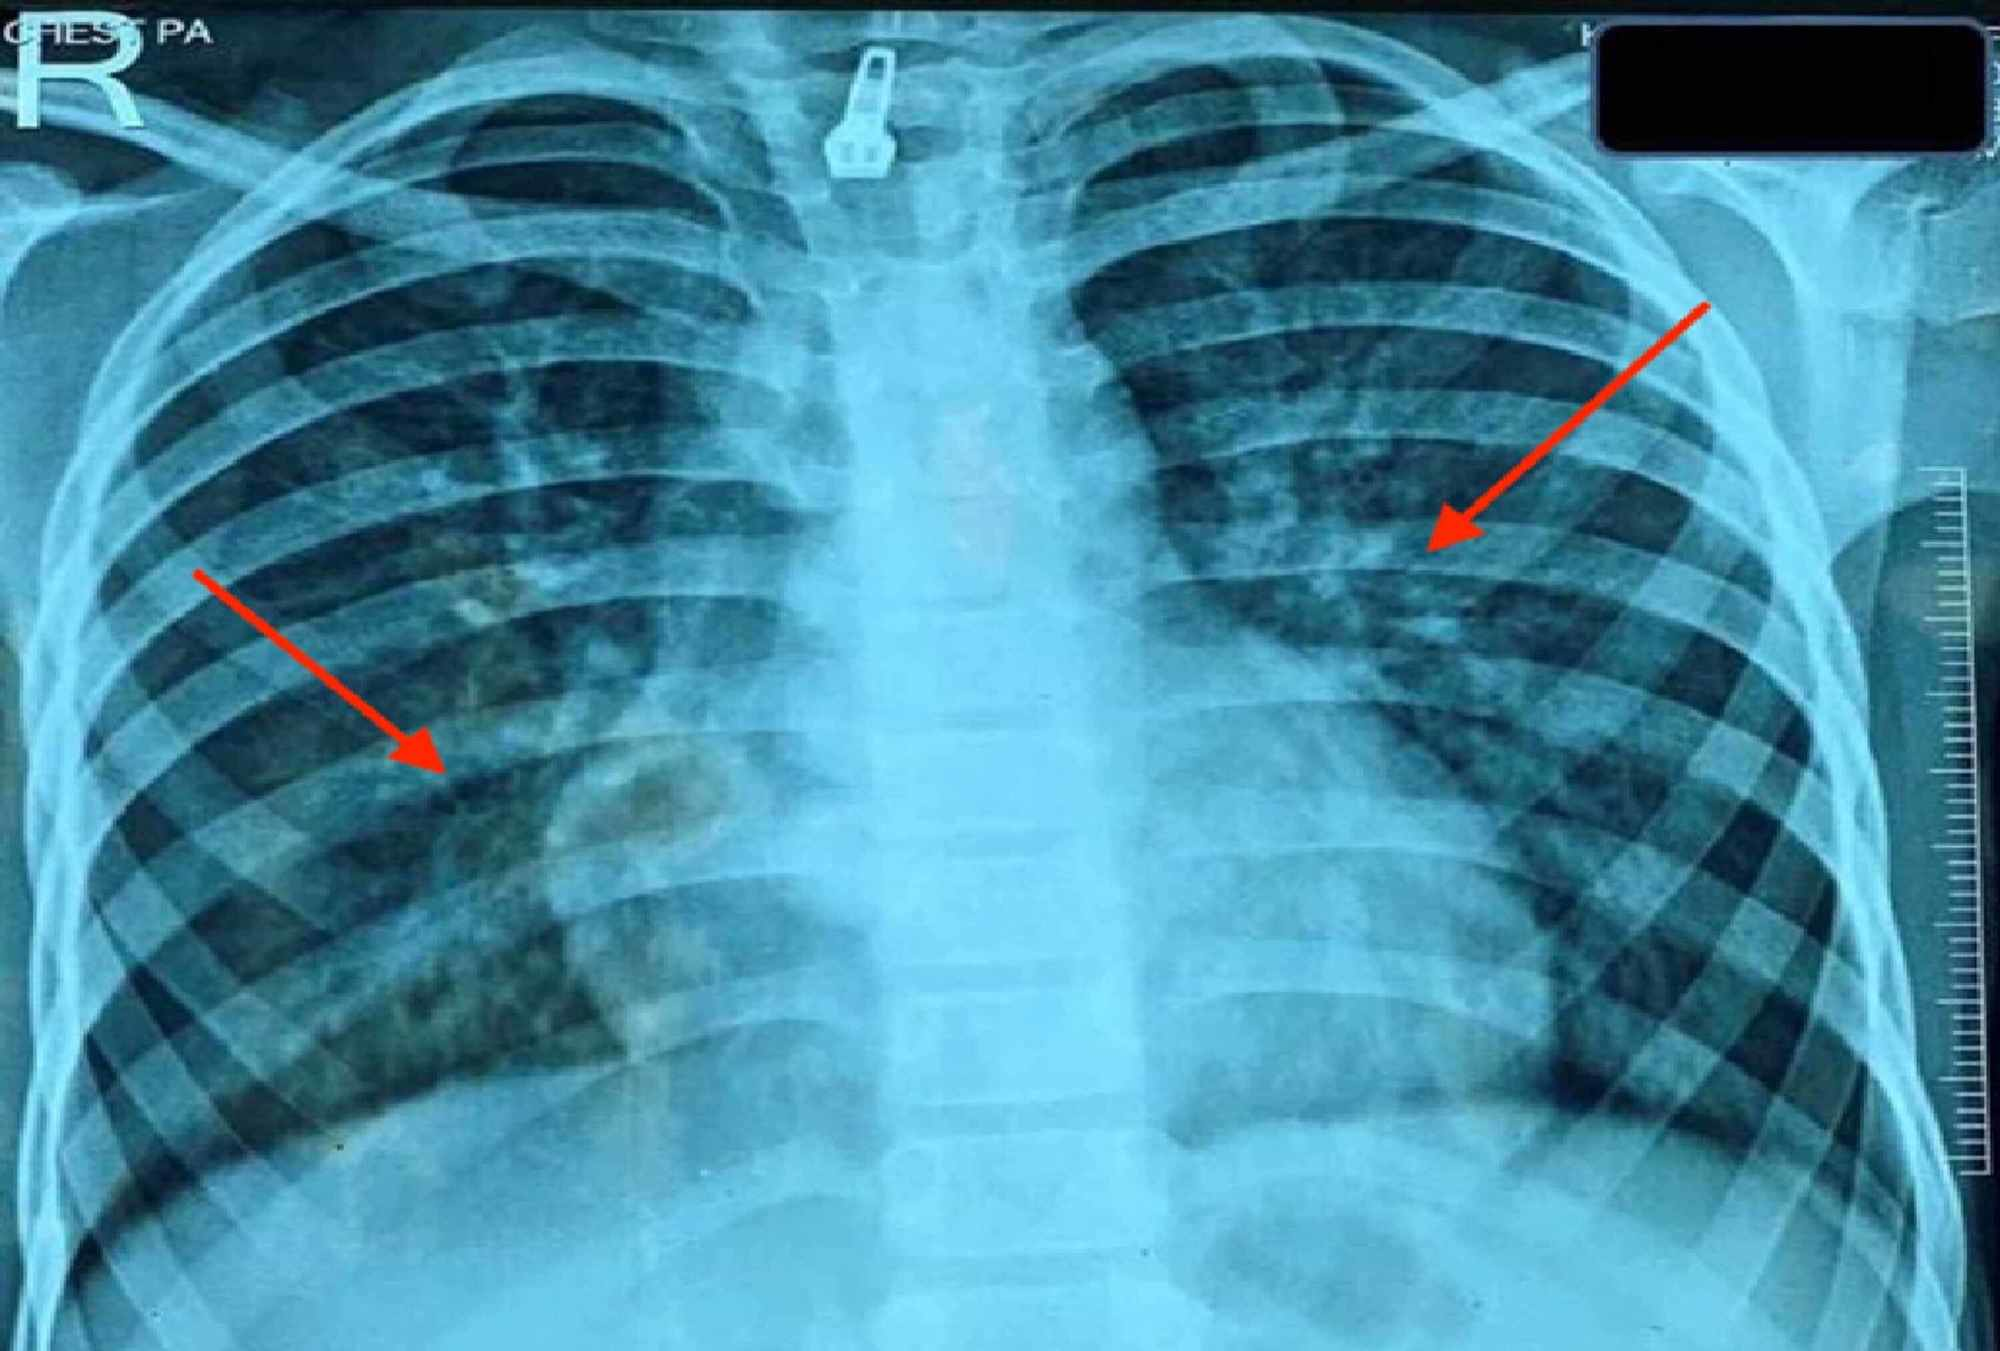

From www.researchgate.net

Radiological and pathological findings of the patient with acute lupus Lupus And Lungs systemic lupus erythematosus (sle) is a chronic, autoimmune disorder that can present. learn how lupus can cause pleuritis, pneumonitis, interstitial lung disease, and pulmonary emboli in the lungs and pulmonary system. learn how lupus can affect the lungs and cause inflammation, infection, blood clots, and scarring. systemic lupus erythematosus (sle) is a chronic systemic autoimmune disease. Lupus And Lungs.